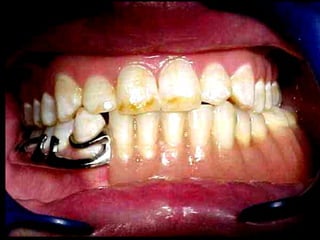

La periodontitis, denominada comúnmente piorrea, es una enfermedad que

inicialmente puede cursar con gingivitis, para luego proseguir con una pérdida de

inserción colágena, recesión gingival, e incluso la pérdida de hueso, en el caso de

no ser tratada, dejar sin soporte óseo al diente. La pérdida de dicho soporte

implica la pérdida irreparable del diente mismo.

De etiología bacteriana que afecta al periodonto (el tejido de sostén de los dientes,

constituido por la encía, el hueso alveolar, el cemento radicular y el ligamento

periodontal) se manifiesta más comúnmente en adultos mayores de 35 años, pero

puede iniciarse en edades más tempranas.

Periodontitis

Una periodontitis según su grado de afectación dental se clasifica en: leve,

moderada o grave. Y según su extensión se denomina: localizada o

generalizada.

Las periodontitis desde 1999 se han clasificado (ASP) en: crónicas,

agresivas y asociada a estados sistémicos.